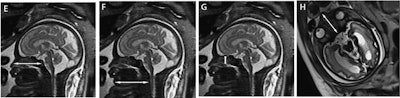

MR images shows fetal measurements for maximal nasal length between the nasal tip and the posterior wall of the nasopharynx (E, white arrow), mandibular vertebral length (F, white arrow), septal height (G, white arrow), and septal length (H, white arrow). Images courtesy of EJR."Novel facial biometric parameters that correlate with [gestational age] hold cardinal information for the prenatal evaluation of facial development and thus surface the need for additional research in order to asses these findings as radiologic markers for facial structural pathologies," wrote Dr. Arik Toren from Sheba Medical Center in Ramat Gan, Israel, and colleagues.

As for gender differences, males had a longer septal length, or the distance between the bridge of the nose at the nasal base and the sphenoid; biparietal diameter, which is the distance between the two temples; and maximal nasal length, which is the distance between the nasal tip and the posterior wall of the nasopharynx. Females, meanwhile, had a wider inferior facial angle.